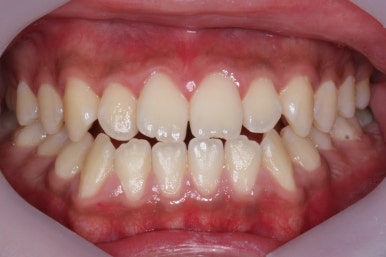

치료 종료 후의 모습입니다.

부산주걱턱교정 키다리아저씨치과에서 이번 환자분 치료에 걸린 총 기간은 1년 4개월이였고, 수술 전 교정 10개월과 수술, 수술 후 교정은 4개월 가량이 걸렸습니다.

주걱턱 경향이 사라졌고, 그에 따라 입술 형태나 웃는 모습, 교합 등등 모든 면에서 개선되었습니다.

전후사진을 비교해 보겠습니다.

양악수술을 통해서 얼굴 모습이 미적으로 많이 개선되었습니다.

뒤집어진 U자형의 입술도 개선되었고, 웃을 때 어금니가 내려와 있던 모습도 많이 개선되었습니다.